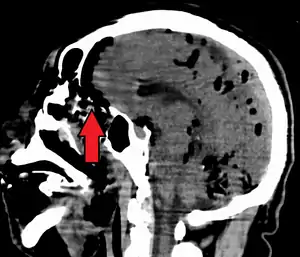

Pneumocephalus is the presence of air or gas within the cranial cavity. It is usually associated with disruption of the skull: after head and facial trauma, tumors of the skull base, after neurosurgery or otorhinolaryngology, and rarely, spontaneously. Pneumocephalus can occur in scuba diving, but is very rare in this context.

| Pneumocephalus and comminuted fracture of the frontal sinus |

If there is a valve mechanism which allows air to enter the skull but prevents it from escaping, a tension pneumocephalus can occur (similar to what can happen in a tension pneumothorax).

CT scans of patients with a tension pneumocephalus typically show air that compresses the frontal lobes of the brain, which results in a tented appearance of the brain in the skull known as the Mount Fuji sign.[1][2][3] The name is derived from the resemblance of the brain to Mount Fuji in Japan, a volcano known for its symmetrical cone. In typical cases, there is a symmetrical depression near the midline (such as the crater of a volcano), due to intact bridging veins.[3] Its occurrence seems to be limited to tension pneumocephalus (not occurring in pneumocephalus without tension).[4] The sign was first described by a team of Japanese neurosurgeons.[5]